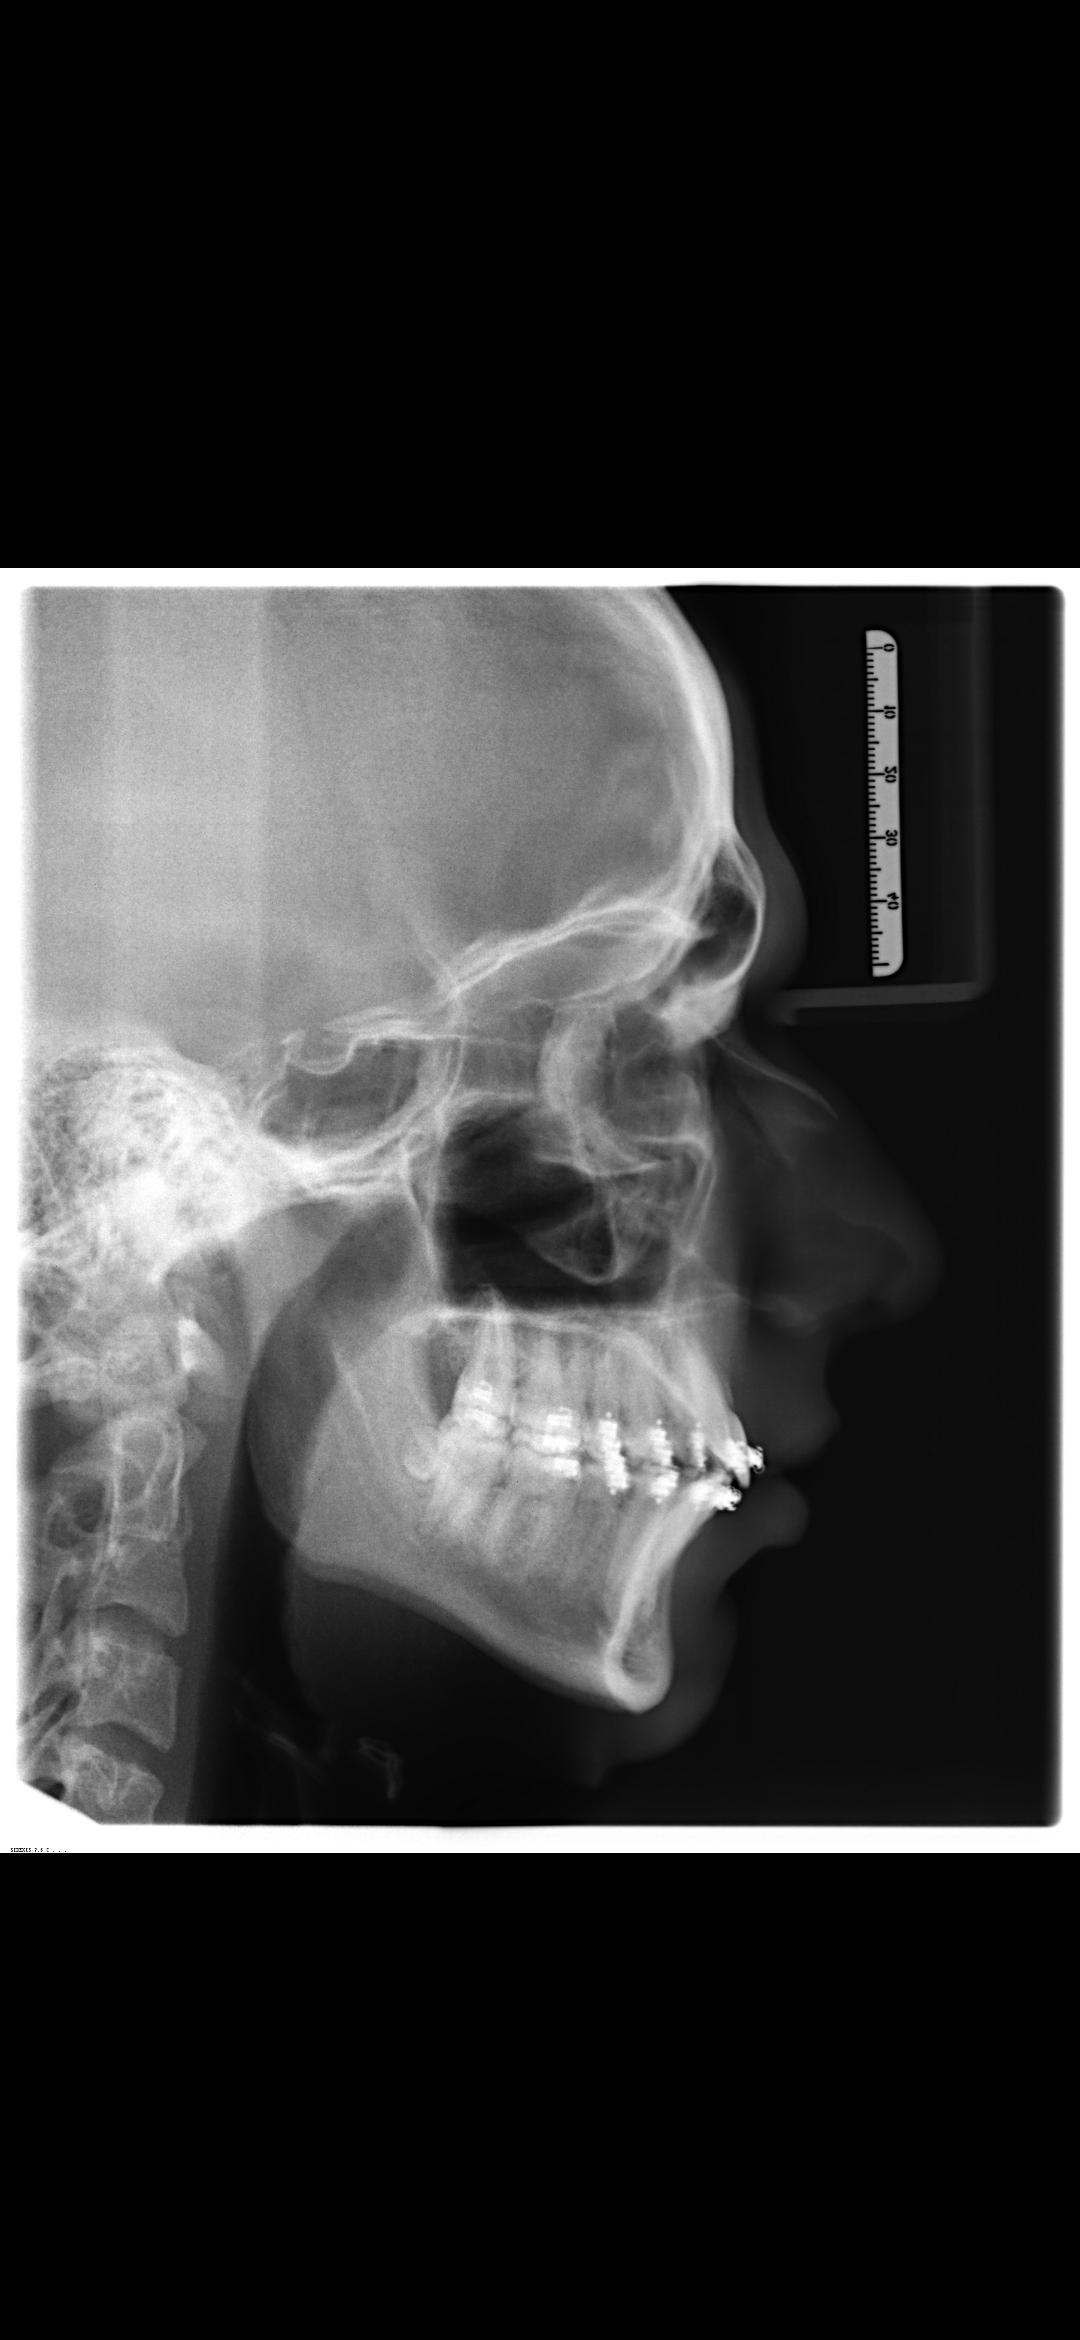

I'm getting bimax + genioplasty in about 4 weeks, but i keep seeing bimaxresults that didn't lead to an ascension such as this one:

Any ideas on how this happens? Sure the patient's base is an important factor but is it rather the lack of knowledge in planning or the "skill" of the surgeon performing the bimax that leads to results like this?

Any ideas on how this happens? Sure the patient's base is an important factor but is it rather the lack of knowledge in planning or the "skill" of the surgeon performing the bimax that leads to results like this?